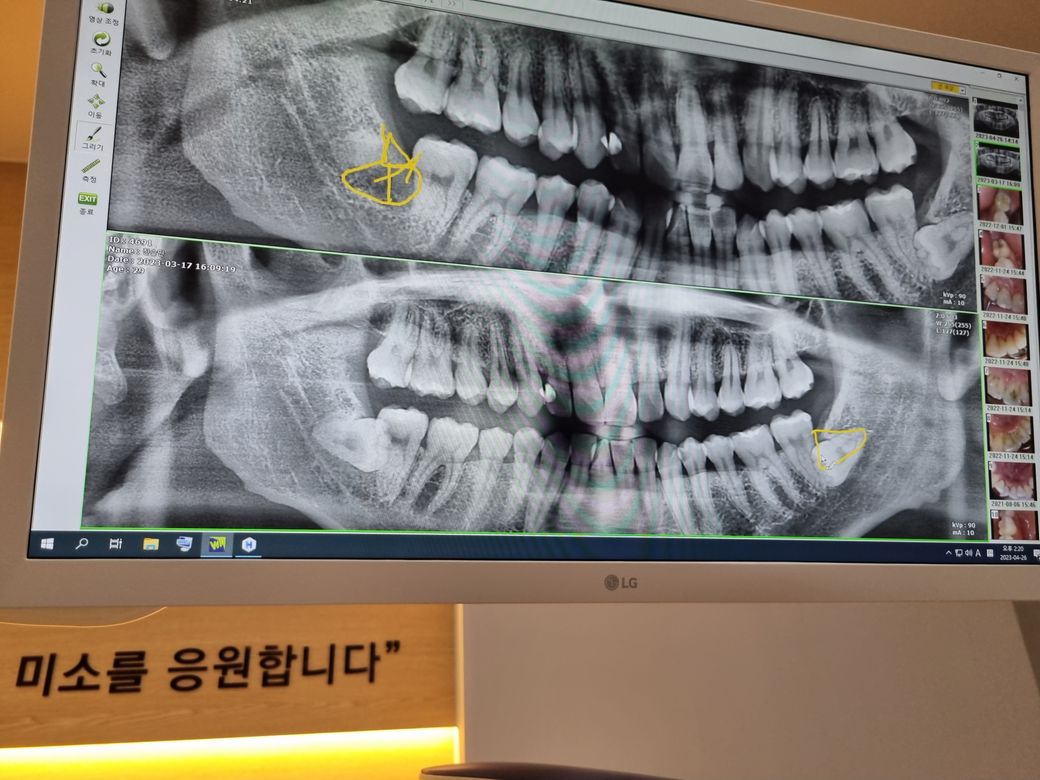

수평매복사랑니인데 이거 빼야 될까요?

우측 사랑니는 발치해서 위 사진이 현재 상태입니다.아래 사진은 원래 상태였구요.. 근데 우측 사랑니 발치회복후 좌측 사랑니 발치를 하려했는데 의사선생님이 극구 말리시네요ㅠㅠ 지금이 뽑을 적기같긴한데.. 발치시 많이 위험한 모양인가요? 어떻게 위험한가요?

좌측 사랑니 놔둬도 괜찮은 사랑니인가요? 훗날에 문제 일으킬 가능성 없을까요?? 가능성이 있다면 어떤 경우가 있을지 언질해주세요.

도와주세요 제발.. 아래는 표시안된 깨끗한 사진입니다.

• 1번 째 사진

좌측 아래 사랑니는 깊이 매복되어 있으면 밑으로 신경관과 사랑니가 겹쳐 있습니다.

이런경우 발치후 사랑니 바로옆 어금니가 흔들거려 어금니도 뽑을 가능성도 있으며, 신경관 때문에 혀나 입술에 감각이상이 올 가능성도 높습니다. 그러나 현재 29세 이니 이런 위험성 감수하고 발치하여 사랑니 바로옆 살려 보는 것을 추천합니다. 이 상태로 그대로 두면 나중에 사랑니와 어금니를 같이 뽑아야 할 가능성이 많습니다.

좌측 아래 사랑니는 깊이도 깊이지만 신경과 굉장히 가까워 보이네요. 신경손상 위험이 강해서 발치하지 말라고 하시는거 같습니다. 그리고 잇몸뼈 깊숙히 뭍혀 잇어서 발치를 안하셔도 크게 문제가 되진 않을것같습니다.